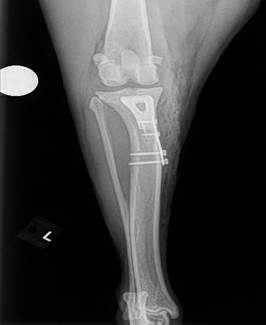

Tibial Tuberosity Advancement (TTA)

This procedure is used to treat cruciate ligament tears by stabilizing the knee joint and altering the forces acting on it. It’s typically recommended for select dogs with specific knee structure and activity levels.